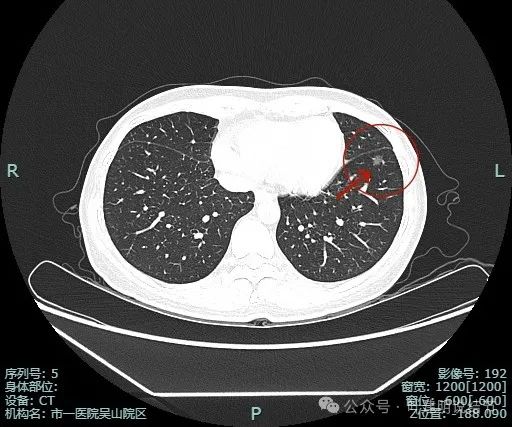

先看非薄层影像:

左肺淡磨玻璃结节,轮廓与边界较为清楚。

有微小血管走向病灶,而且病灶表面欠平滑。